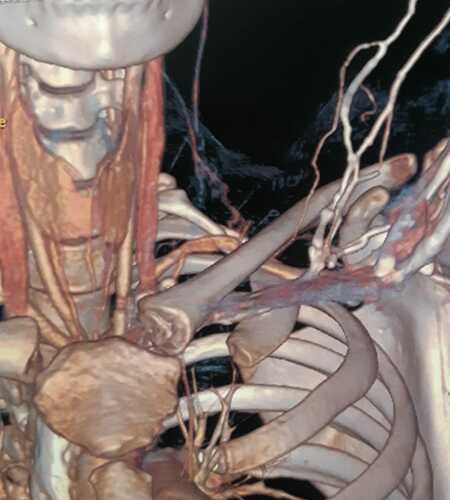

Ao se passarem 3 meses, retornei ao médico com novos exames, já curada da trombose de membro superior, recebi a notícia de uma compressão arterial, mais especificamente Síndrome do Desfiladeiro Torácico. Em exames mais específicos, descobriu-se também uma Costela Cervical, que ajudou para com a compressão da artéria.